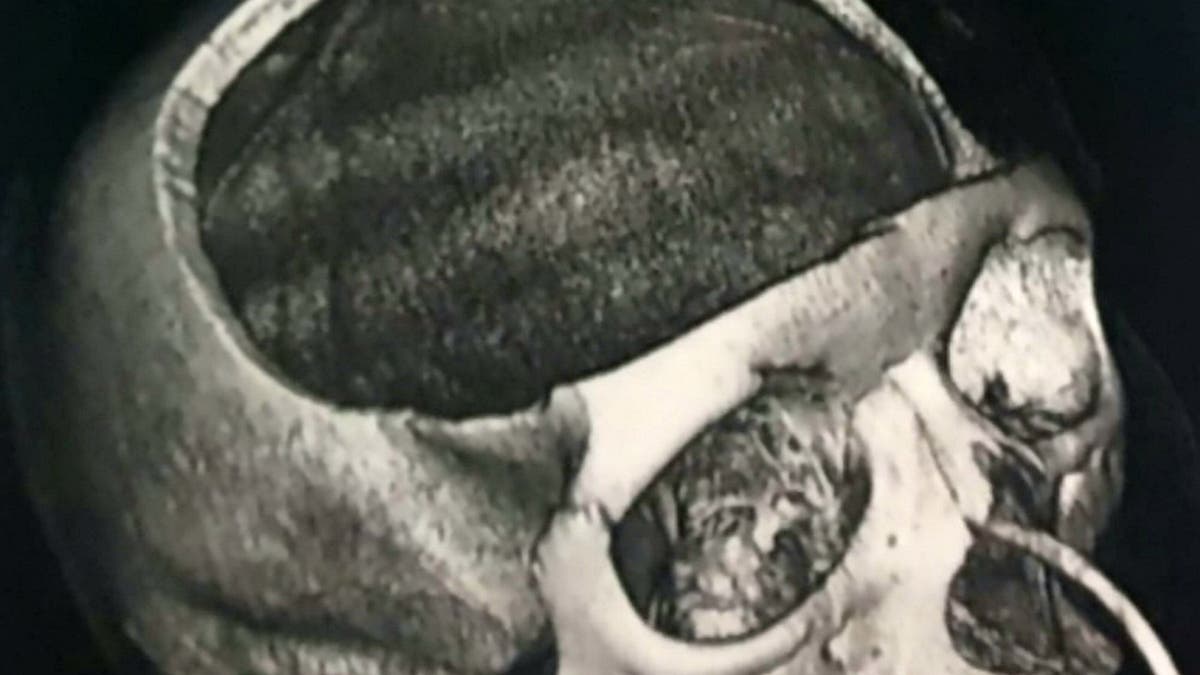

The 22-year-old had the front part of her skull removed following the scary incident. (SWNS)

Blake, who was in a coma for 19 days following the incident, says she underwent surgery to remove the front part of her skull in an attempt to reduce swelling and pressure on her brain. Her skull was eventually re-attached using titanium plates and screws, the Daily Mail reports. She has since undergone two other surgeries.